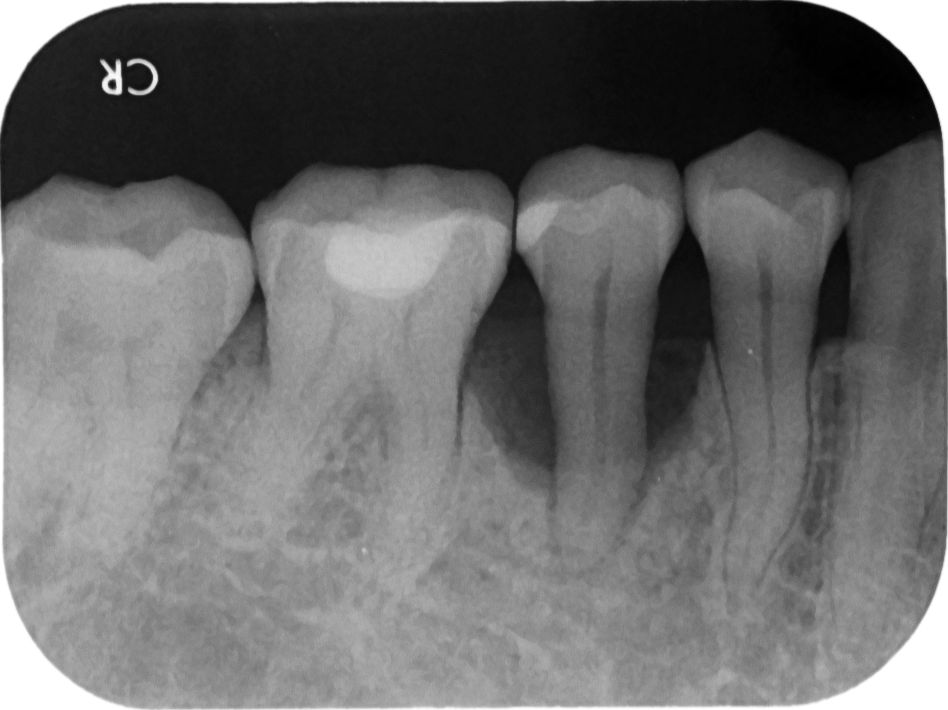

「趙小姐,您因為下面缺牙太久,導致上顎的對咬牙長下來,佔據掉原來下面牙齒的空間,所以沒有空間做假牙。」

「對,有時候拖太久甚至牙齒周圍的骨頭也會跟著長下來。」

「而趙小姐您的狀況更嚴重,上面牙齒幾乎已咬到下面的牙肉,如果以您的現況是無法製作假牙的。」林醫師回答。

「解決之道有三種方法,第一種,需要把上面長下來的牙齒修短,下顎在植牙時,也要修磨掉一些骨頭,如此往上往下爭取一些空間,才有足夠的垂直高度來製作假牙。」

「但是,由於牙齒修磨後會傷到牙齒的神經,所以牙齒修磨完會痛,那就需預先做『抽神經』的治療,也就是做『蓄意性的根管治療(intentional endodontic treatment)』,比較麻煩,但又不得不做。」